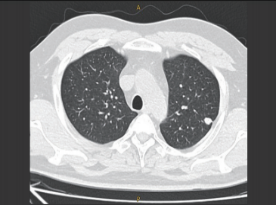

CT成(chéng)像系統